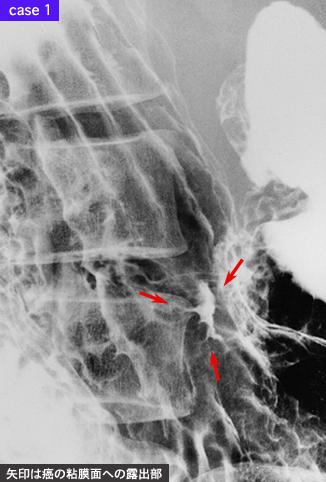

疾病(病理主体)的分类恶性上皮性肿瘤/腺癌

部位(按器官分)胃(部位)/2个以上

检查方法X线

肿瘤的肉眼分类4型(弥漫浸润型)/

肿瘤最大直径40以上

肿瘤的深度s(a)